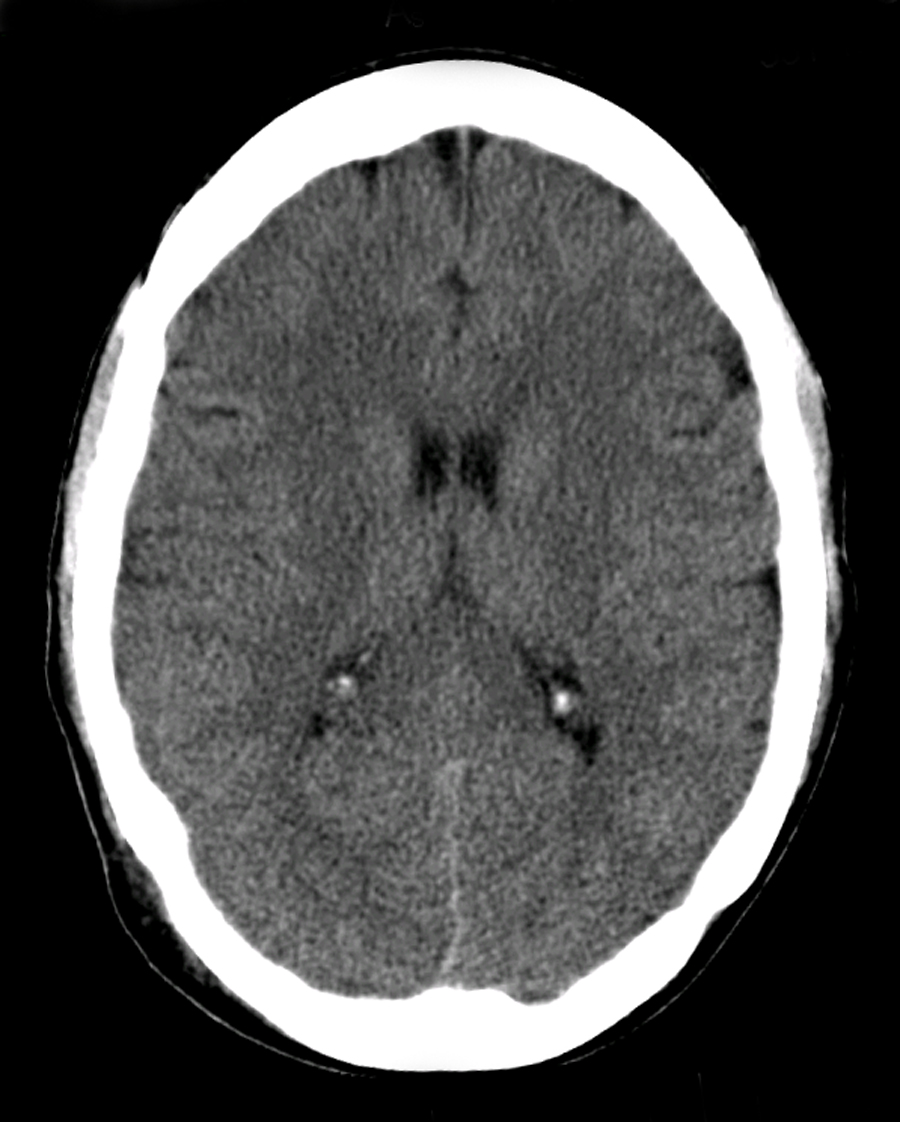

Standard adult head phantom with brain parenchyma, CSF, skull, and ventricles